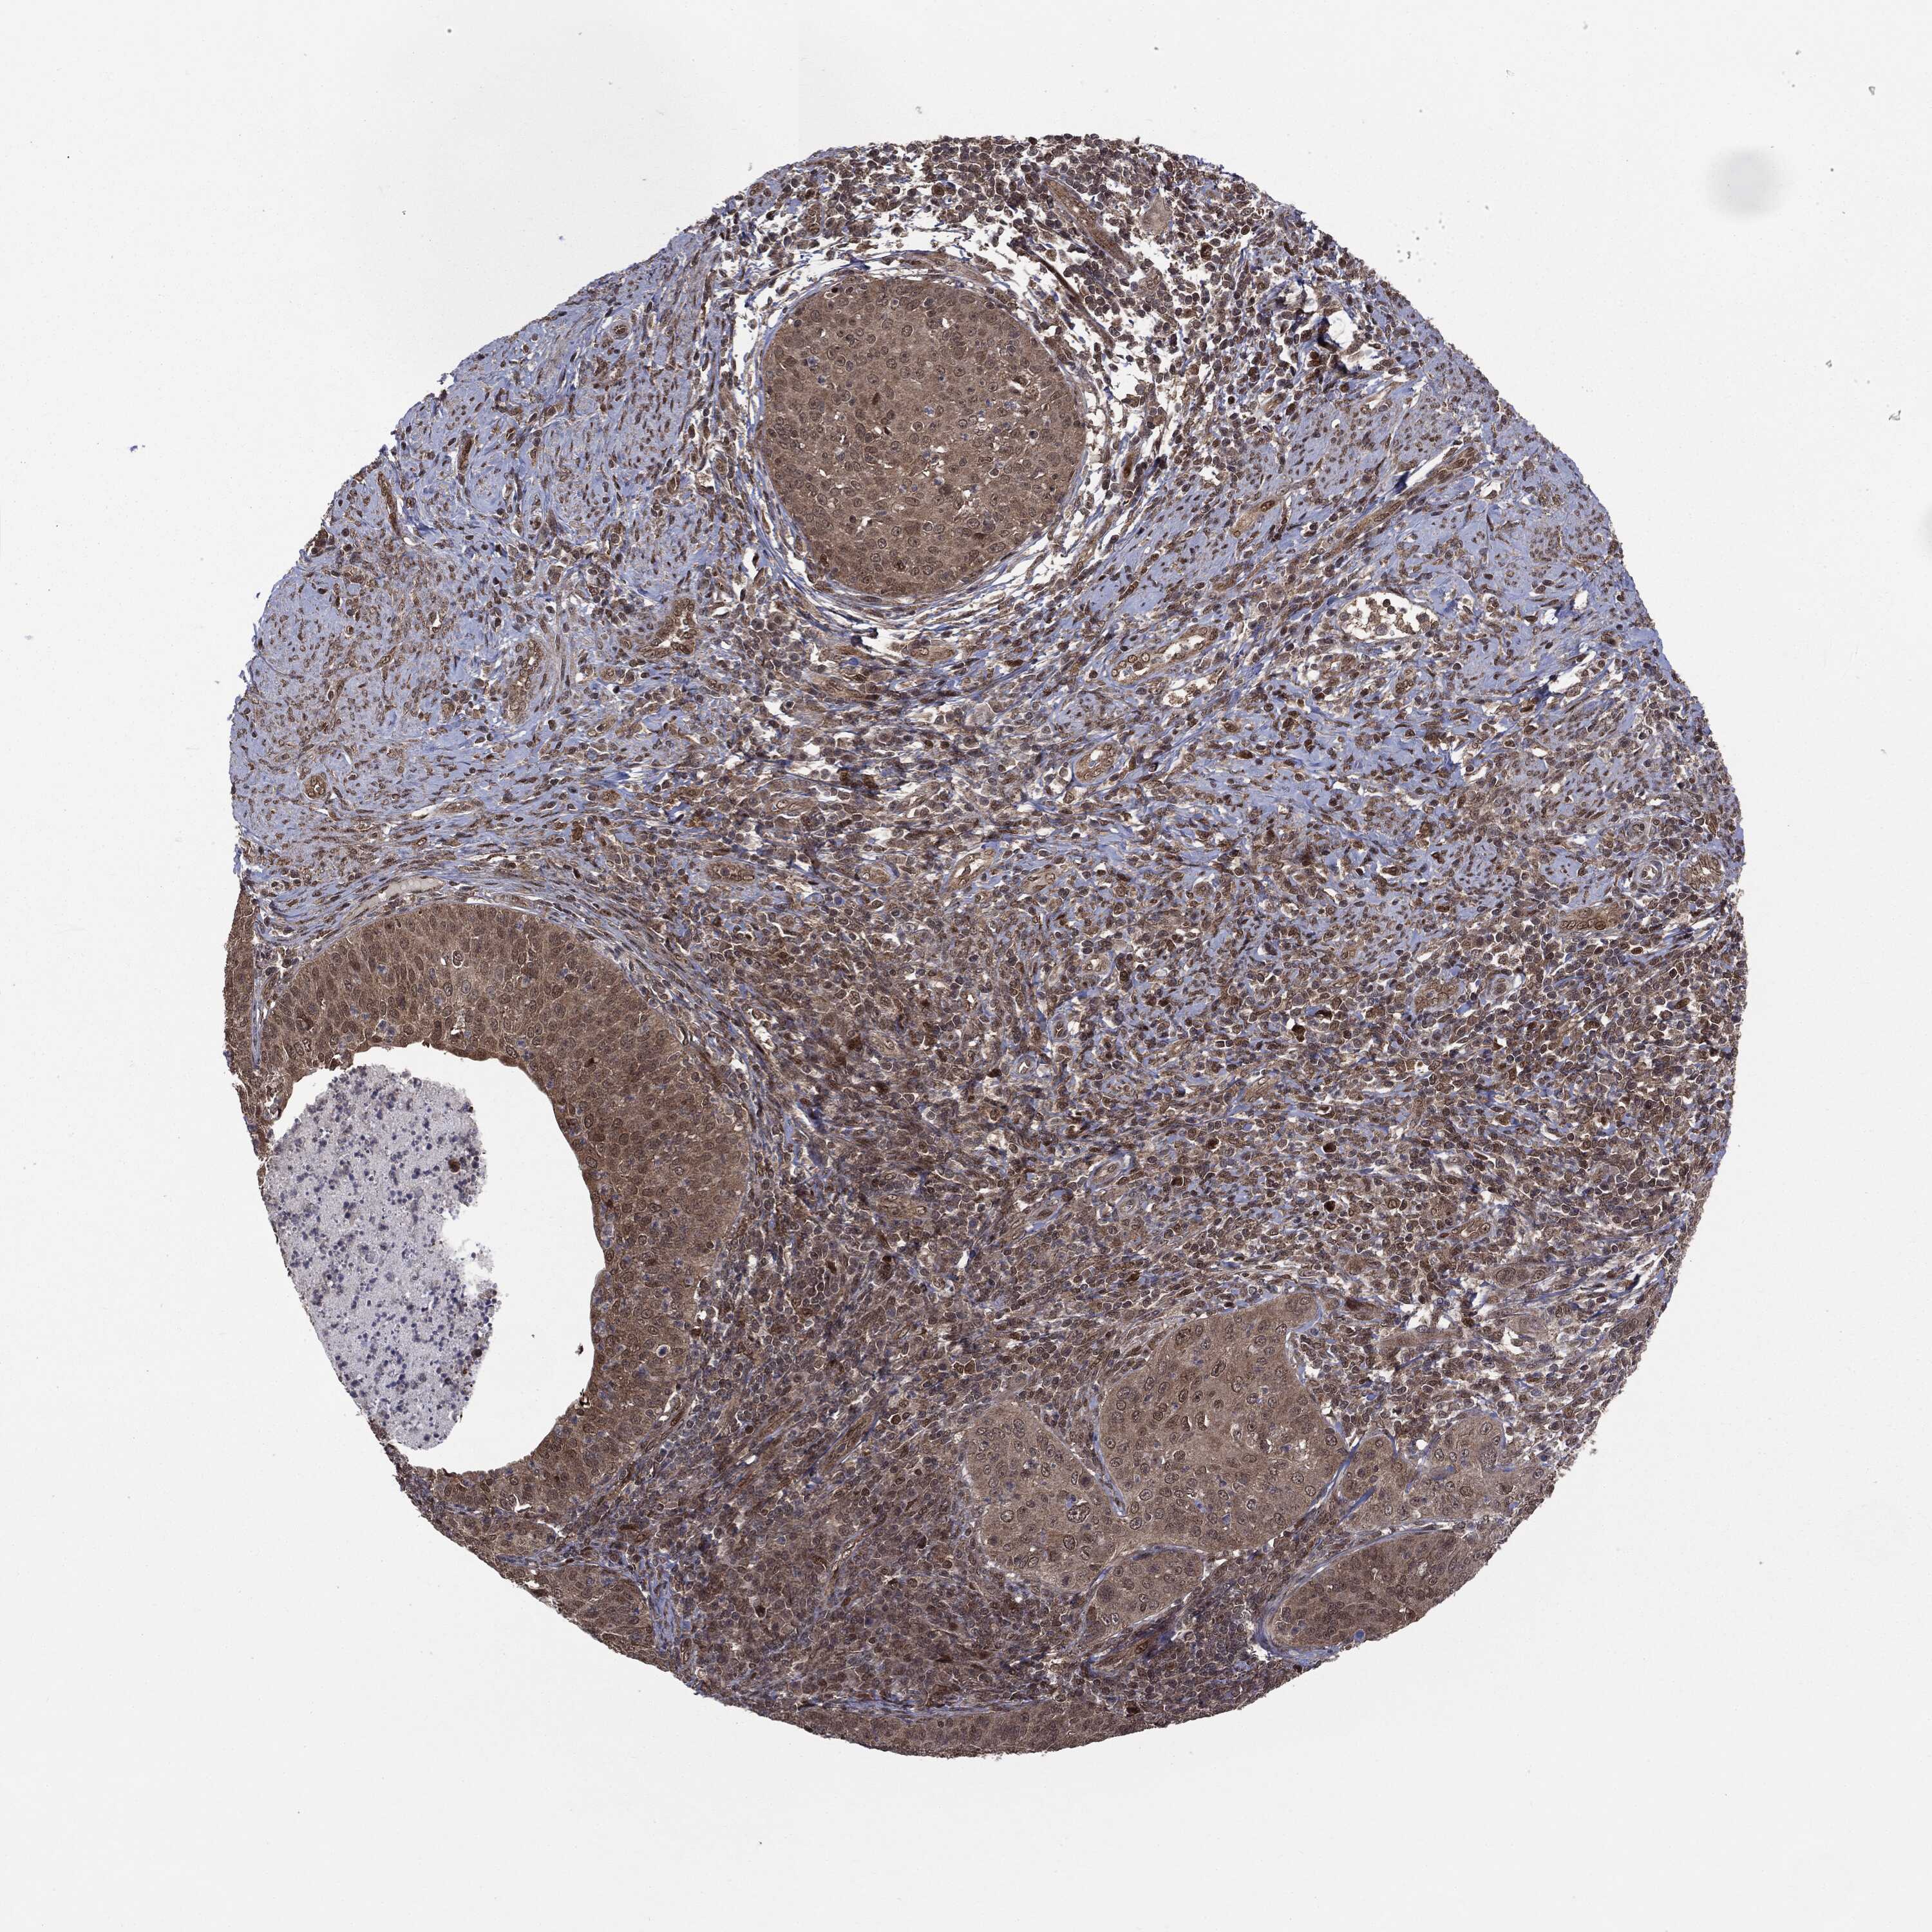

CERVICAL CANCER - Protein expressioni

A mouse-over function shows sample information and annotation data. Click on an image to view it in a full screen mode. Samples can be filtered based on level of antibody staining by selecting one or several of the following categories: high, medium, low and not detected. The assay and annotation is described here.

Note that samples used for immunohistochemistry by the Human Protein Atlas do not correspond to samples in the TCGA dataset.

Antibody stainingi

Antibody staining in the annotated cell types in the current human tissue is reported as not detected, low, medium, or high, based on conventional immunohistochemistry profiling in selected tissues. This score is based on the combination of the staining intensity and fraction of stained cells.

Each image is clickable and will lead to virtual microscopy that enables deeper exploration of all samples and also displays staining intensity scores, fraction scores and subcellular localization as well as patient and tissue information for each sample.

HPA005695

CAB022068

CAB035999

CAB080052

CAB080054

CAB080098

Staining

High

Medium

Low

Not detected

Intensity

Strong

Moderate

Weak

Negative

Quantity

>75%

75%-25%

<25%

None

Location

Nuclear

Cytoplasmic/membranous

Cytoplasmic/membranous,nuclear

Squamous cell carcinoma, NOS

Adenocarcinoma, NOS